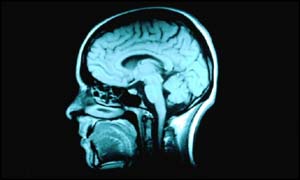

Ultrasound hope for brain diseases

Doctors believe they have found a way of treating patients with serious brain diseases without the need for surgery.

Researchers in the United States have suggested that sound waves could play a key role in helping to get drugs into the brain.

At present, patients in need of targeted drug treatment in the brain must undergo surgery.

This is because drugs cannot enter the brain via the bloodstream.

A protective layer around the brain - the so-called blood-brain barrier - prevents drugs and other substances from passing into the brain.

But Dr Ferenc Jolesz and colleagues at Brigham and Women's Hospital in Boston believe ultrasound could be used to overcome this problem.

They have found a way to temporarily open the barrier to allow drugs and genes to be delivered into specific parts of the brain.